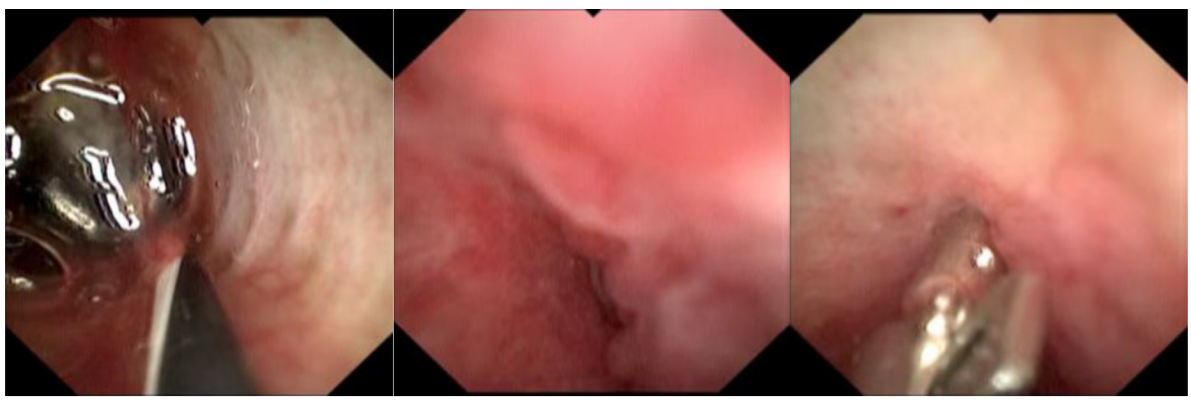

8. 贲门失弛缓内镜下括约肌切开治疗。

POEM治疗贲门失弛缓症